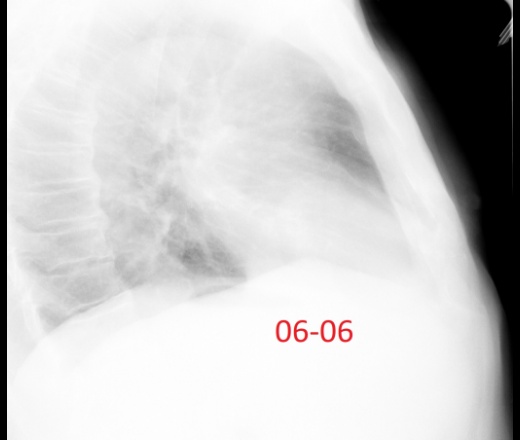

Мужчина 60лет. Диагностическая флюорография, 22 мая был поставлен диагноз пневмония с\д справа, пришел к нам на контроль второй раз.  Думаю все хорошо можно отпускать? Ваше мнение коллеги?

Да, динамика положительная, 4 сегмент с гиповентиляцией. Ограничился бы рентген контролем ч\з 1-1.5 мес.

Да нет, купол диафрагмы. (с учетом 22.05, 06.06.)

По всей видимости плеврит перенесен...

Динамика положительная. Слева облитерация костодиафрагмального синуса вследствии перенесенного плеврита